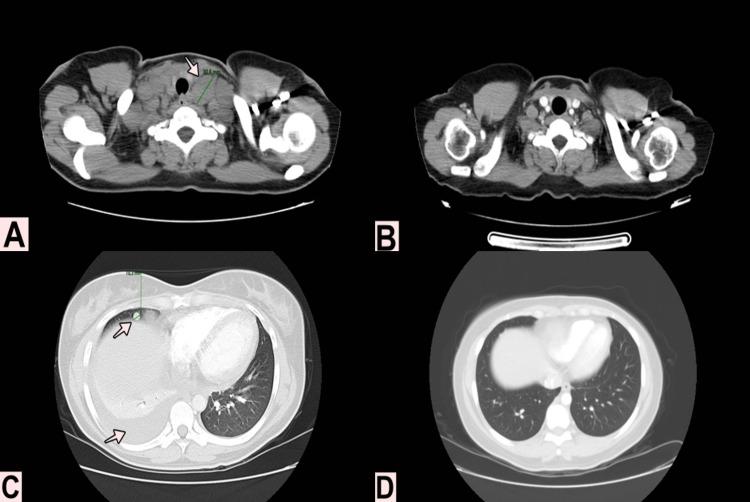

Wilms' tumor is childhood's most common renal tumor, and its presentation in the adult age is extremely rare. Due to the low frequency in adults, no standard management guidelines are available for this population, also the natural history of the disease and management is unclear. We present a case report of a 31-year-old woman with metastatic Wilms' tumor, with lymph node, lung and liver involvement; systemic treatment with chemotherapy was started, with complete clinical response. Finally, a literature review is performed to showcase the differences in the clinical course, prognosis, and treatment alternatives, in adult disease compared to childhood.

肾母细胞瘤是儿童期最常见的肾肿瘤,在成人中极为罕见。由于在成人中发病率低,尚无针对该人群的标准管理指南,而且该疾病的自然病程和管理尚不清楚。我们报告一例31岁转移性肾母细胞瘤女性病例,伴有淋巴结、肺和肝转移;开始进行化疗全身治疗,临床完全缓解。最后,进行文献综述以展示成人疾病与儿童疾病在临床病程、预后和治疗选择上的差异。